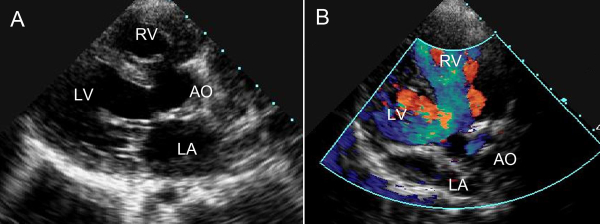

5、心脏:各种先天性心脏病及后天性心脏病超声诊断。

彩色多普勒超声对心脏及血管病变的诊断:

彩色多普勒超声能够同时评价血管的二维结构和实时血流动力学变化。我院超声科已开展此项技术。

1、超声心动图能够显示心脏结构,观察血流状态,评估心脏功能及治疗效果,其临床应用价值已得到大家的公认。